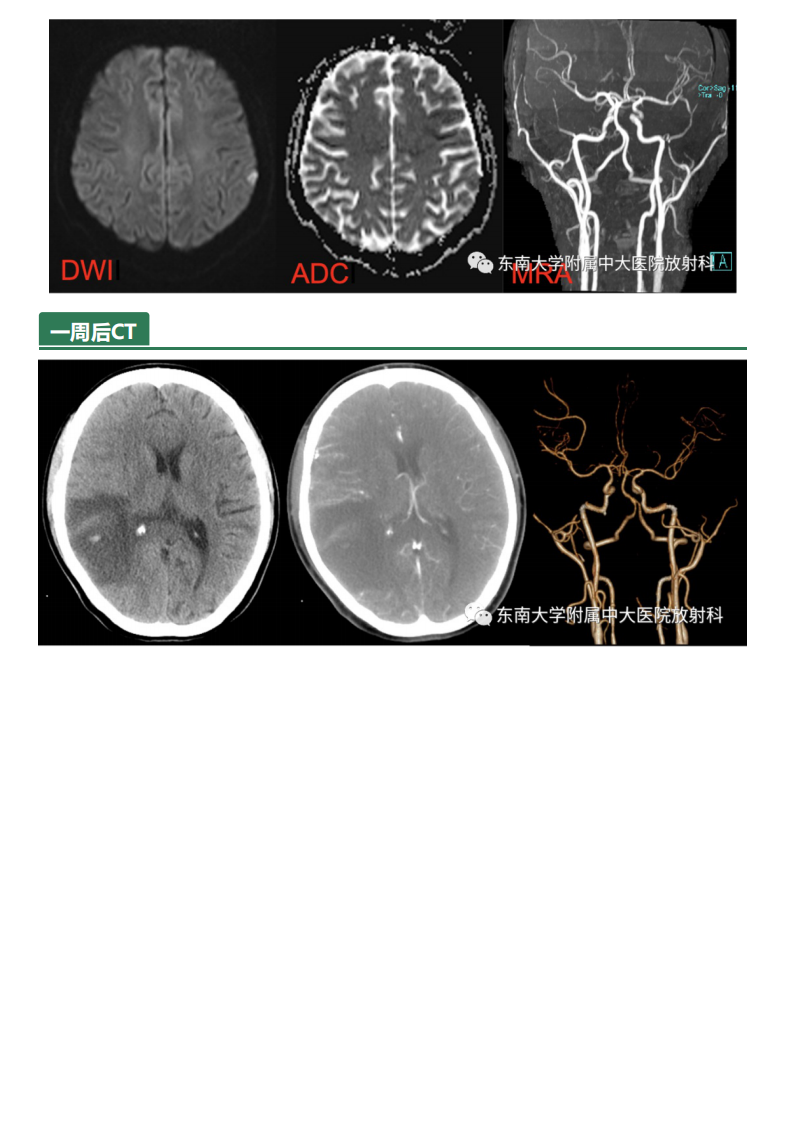

20210611_2【晨读结果公布】2021.06.10多系统疾病——SLE相关疾病.pdf